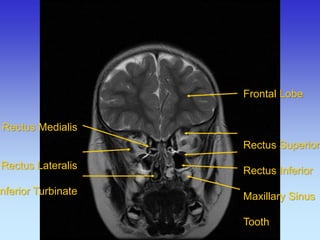

Frontal Lobe Rectus Superior Rectus Inferior Maxillary Sinus Tooth